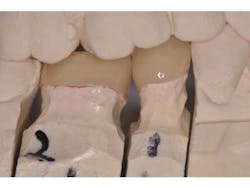

A patient presents with splinted provisional crowns on teeth Nos. 29 and 30 (Fig. 1). The provisionals were splinted to aid retention during the laboratory fabrication phase. The treatment plan called for all-ceramic restorations that could take advantage of resin cement bonding technology, thus the preparation margins were kept supragingival. Lithium disilicate restorations (e.max, Ivoclar) were created monolithically, meaning that no veneering feldspathic porcelain was required (Fig. 2).